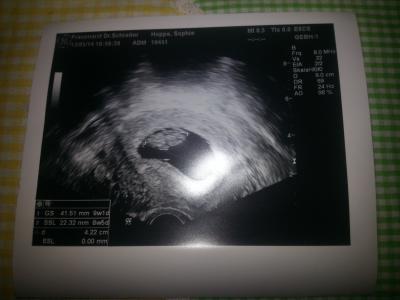

also der wurm kommt im dez. sie ist in der 9ssw..jaja wie war das Sprichwort mit Ostern-eiern und weihnachten ..naja wird bis kurz vor Geburt bei uns bleiben und dann in eigene 4 wände ziehen..anbei Foto vom baby